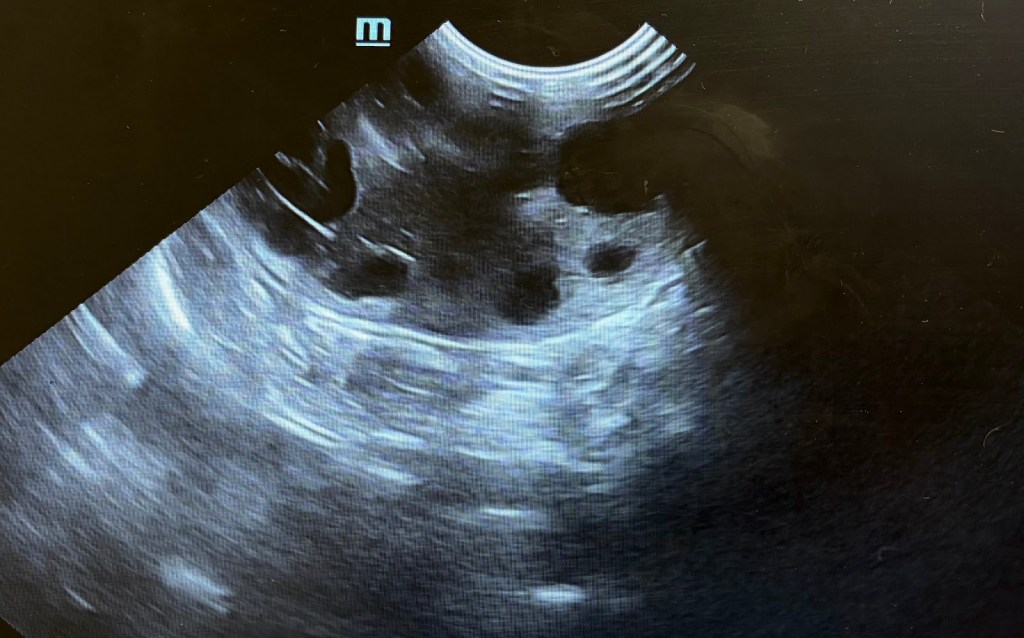

Hastalığın tanısında ve takibinde en sık kullanılan yöntem ultrasonografidir. Ultrason taramasında, en az bir böbrekte PBH ile karakterize olan en az bir adet yuvarlak şekilli, anekoik veya hipoekoik kist yapısı görülmesi, hekimin hastalıktan şüphelenmesini sağlar. Eğer yukarıda bahsedilen ırklardan bir kediyse PBH yönünden hekimi tarafından takibe alınır. Hastalığın ilk dönemlerinde kistlerin küçük ve az sayıda olduğu gözlenirken; ilerleyen dönemlerde görüntüde, böbreğin normal sınırlarını aşan ve şeklini bozan çok sayıda kist olduğu görülebilir. Ayrıca bu kedilerde nadir de olsa diğer organlarda da kistler oluşabileceği için o bölgeler de ultrasonografik olarak kontrol edilmelidir.

Ultrasonda Polikistik Böbrek görüntüsü